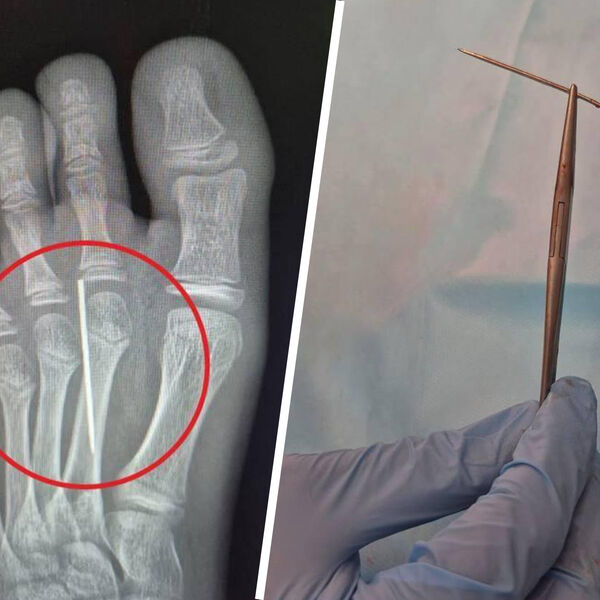

«Врачи визуализировали на рентгене инородное тело и с помощью специального инструмента «Москит» аккуратно извлекли иголку. На все ушло около трех минут», — поделились в Минздраве.